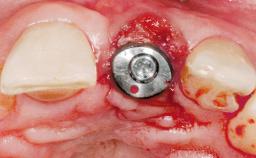

Late Placement of an Implant in a Maxillary Left Central Incisor Site

A 30-year-old female patient had lost tooth 21 and was referred to our clinic for consultation and treatment. Due to advanced apical infection, tooth 21 had been extracted two months earlier at another clinic and an acrylic-resin tooth had been bonded to the adjacent teeth. The patient desired implant treatment to avoid any damage to the adjacent natural teeth. While the patient had no history of any systemic disorder, she was a heavy smoker and exhibited medium to advanced periodontitis in the entire jaw. After the initial treatment to achieve a pocket probing depth of less than 4 mm and no bleeding on probing, a decrease in the height of the papillae mesial and distal to the extraction site and overall gingival recession were observed.

Type of Implants One-Piece|Reduced-Diameter

Attachment One-Piece|Reduced-Diameter

Soft Tissue Grafting Simultaneous

Defining Characteristics One missing tooth to be replaced by an implant-borne prosthesis

Placement Protocol Early or late implant placement